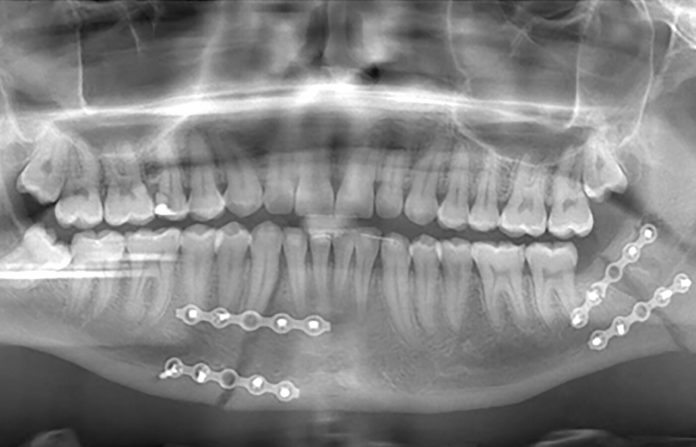

Gabriel Alin Iancu, tânărul de 19 ani din Motru, lovit cu putere în zona fetei de fiul polițistului Petcu de la Poliția Motru, a fost supus la Craiova unei intervenții chirurgicale în zona maxilarului. Apartinatorii tânărului, părinții fiind plecați în străinătate, relatează pentru Gorjeanul că fiul lor s-a prezentat singur la poliție în cursul nopții, după ce Gabriel Sorin Petcu i-a spart maxilarul, în timp ce agresorul era pe urmele lui cu un cuțit. Mama tânărului spune că a luat un avocat din Craiova și că apartinatorii au fost sfătuiți să mai aștepte până la depunerea unei plângeri penale împotriva agresorului.